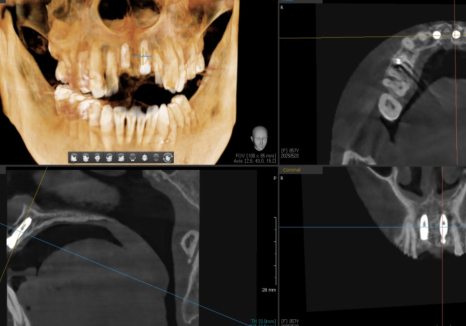

CT로 정확한 위치

확인 후 식립

잇몸 까매짐 원인,증상,치료 방법

250520

그래서 저는 식립 전 CT로

정밀하게 계획을 세우고

식립 후에도 촬영해서 의도한 대로

정확하게 들어갔는지 한 번 더 확인합니다.